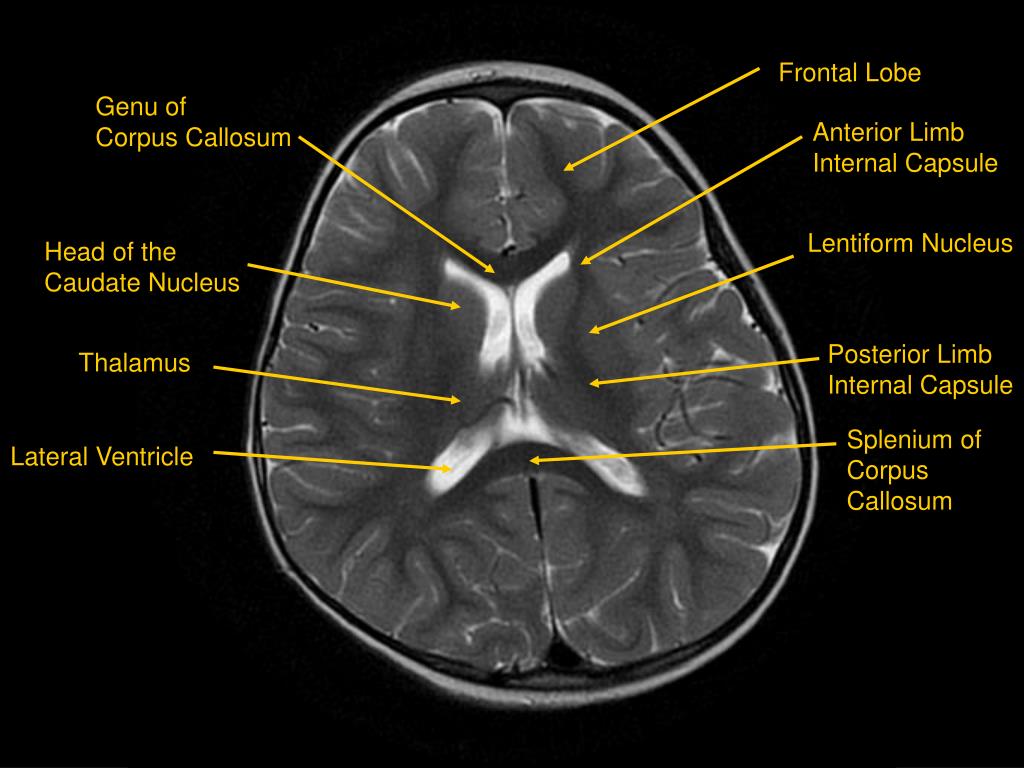

Lateral Mri Brain Labeled . A review of brain magnetic resonance imaging (mri) is used as support. Mri is used to analyze the anatomy of the brain and to identify some pathological conditions such as cerebrovascular incidents, demyelinating and neurodegenerative diseases. The anatomy of the brain is studied by means of axial, coronal and sagittal views. This article lists a series of labeled imaging anatomy cases by body region and modality. Horizontal part of the middle cerebral artery which gives rise to the lateral lenticulostriate arteries which supply most of the basal ganglia. An “overview” of the brain anatomy is offered on this page. From superior to inferior, selected sections demonstrate the structures shown by t2 mri at the level of the vertex (a), lateral ventricles (b), third ventricle (c), midbrain. Brain mri with annotations of major structures. Use the mouse scroll wheel to move the images up and down, or alternatively, use the tiny arrows (→) on both sides of the image to navigate through the images.

This article lists a series of labeled imaging anatomy cases by body region and modality. A review of brain magnetic resonance imaging (mri) is used as support. Horizontal part of the middle cerebral artery which gives rise to the lateral lenticulostriate arteries which supply most of the basal ganglia. Brain mri with annotations of major structures. From superior to inferior, selected sections demonstrate the structures shown by t2 mri at the level of the vertex (a), lateral ventricles (b), third ventricle (c), midbrain. Use the mouse scroll wheel to move the images up and down, or alternatively, use the tiny arrows (→) on both sides of the image to navigate through the images. The anatomy of the brain is studied by means of axial, coronal and sagittal views. Mri is used to analyze the anatomy of the brain and to identify some pathological conditions such as cerebrovascular incidents, demyelinating and neurodegenerative diseases. An “overview” of the brain anatomy is offered on this page.